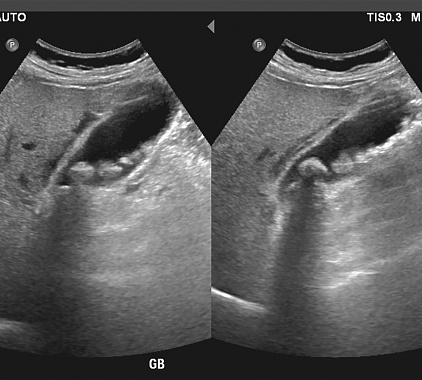

Фотогалерея